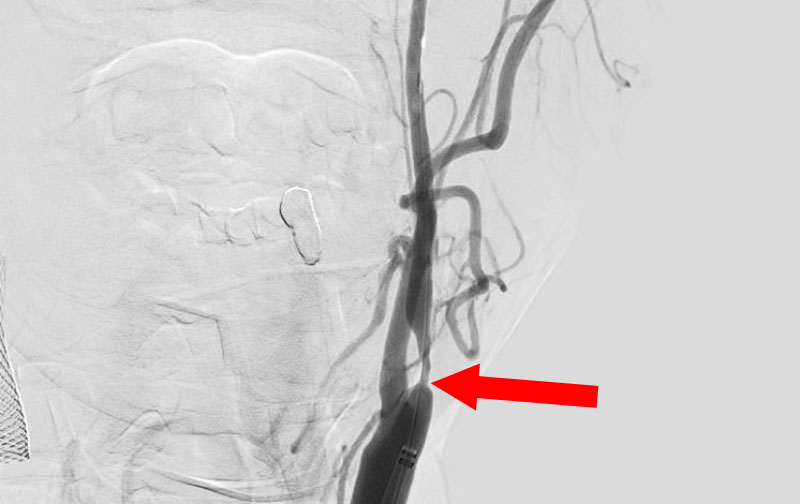

No.1540 手術前

No.1540 手術中

No.1540 手術後

'25年3月

心原性脳塞栓症

80代

救急外来